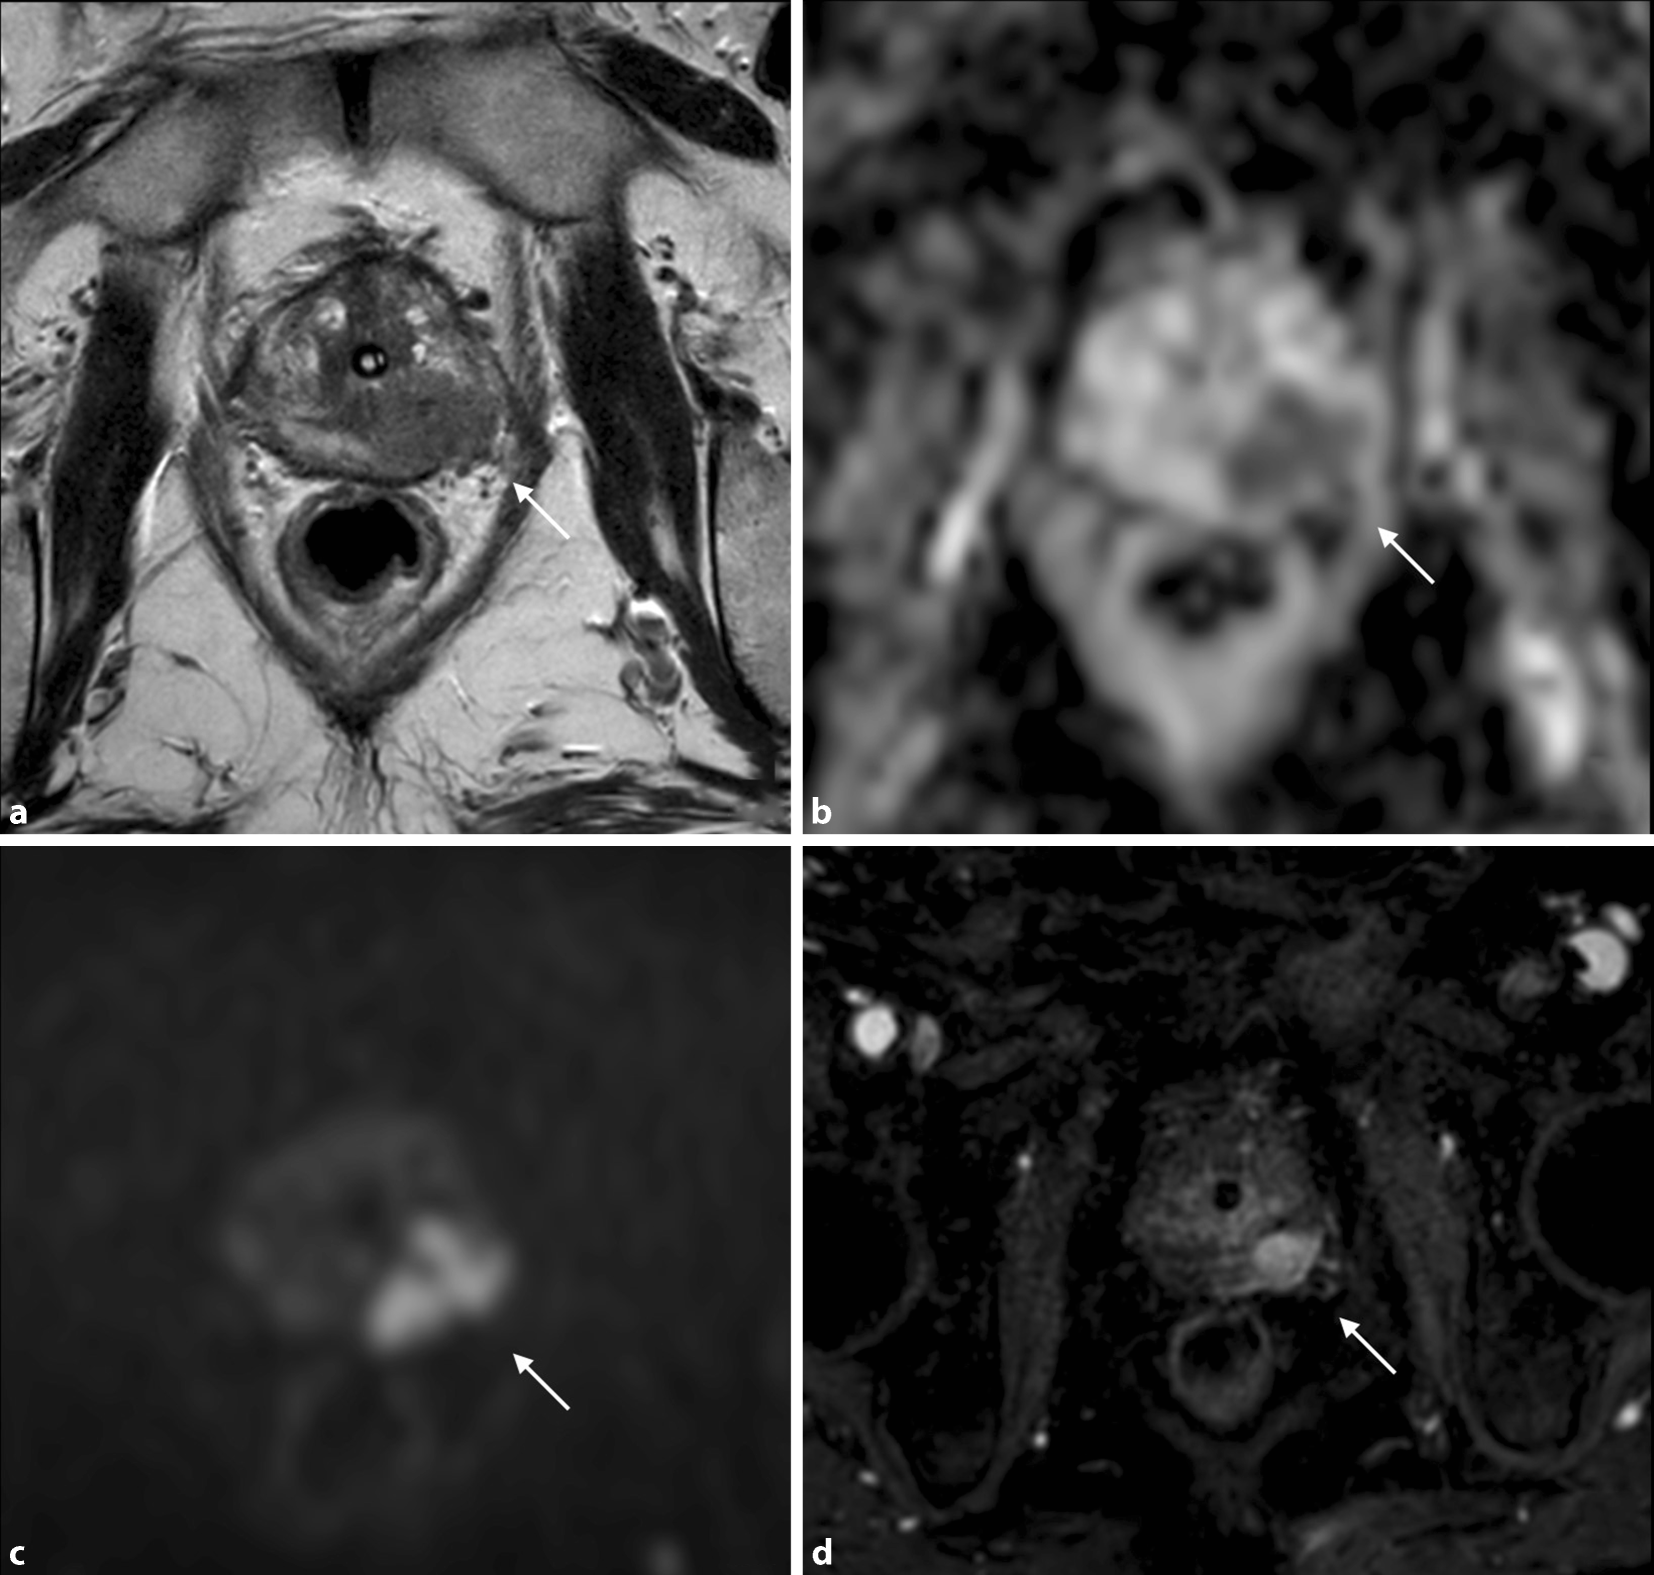

L’IRM multiparamétrique de la prostate (IRMmp) est une modalité radiologique qui combine l’imagerie IRM anatomique avec une ou plusieurs séquences IRM fonctionnelles. C’est actuellement la modalité d’imagerie la plus précise pour détecter, localiser et déterminer le stade du cancer de la prostate. Elle fournit des informations anatomiques en utilisant l’imagerie pondérée en T2, ainsi que des informations métaboliques grâce aux techniques de contraste amélioré (IRM-DCE) et de diffusion (IDP) ([25]; Fig. 1). Elle peut ainsi identifier différents types de lésion.

L’IRM multiparamétrique (IRMmp) montrant une lésion prostatique de la zone périphérique postéro-médiane gauche avec effraction de la capsule prostatique, classé Prostate Imaging Reporting and Data System (PI-RADS) 5. a Séquence anatomique en pondération T2 montrant la lésion sous forme d’une plage en hyposignal. b,c Séquences fonctionnelles de diffusion (ADC et high b‑value DWI) avec hypointensité de signal en ADC et hyperintensité en high b‑value DWI. d Séquence de perfusion dynamique (dynamic contrast enhancement – DCE), montrant un rehaussement intense et précoce de la lésion